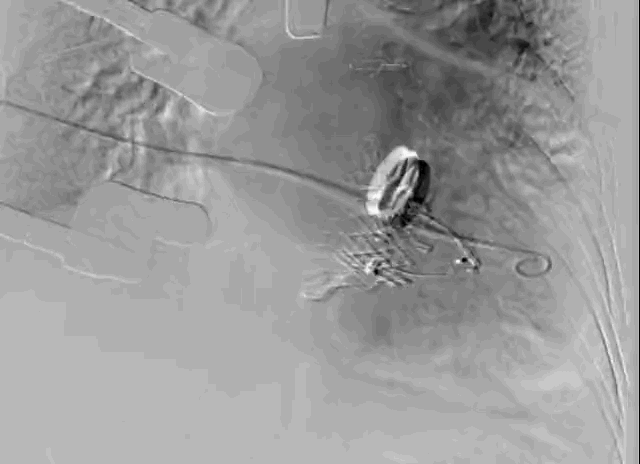

长海医院心外科徐志云、陆方林团队综合该患者CT、超声检查结果,对该患者的情况进行了充分的评估和讨论,决定采用LuX-Valve®瓣膜系统对患者进行微创治疗。手术于7月12日上午在长海医院导管室进行。根据术前CT的测量结果,选择使用JS/TTVI-30-55型号的LuX-Valve®瓣膜。只需在患者右侧第五肋间开一个小孔,经右心房穿刺,在心脏不停跳的情况下,用导管将介入瓣送入右心室,反复调整瓣膜位置,最终超声确认无瓣周漏后对瓣膜进行锚定。术后超声和造影显示瓣膜位置良好,无明显反流。

瓣膜植入前右心室造影